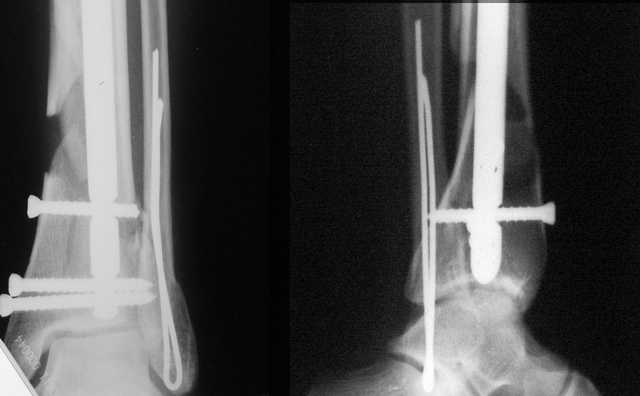

АЧ>Какие тут аргументы в пользу выбора пластины, а не интрамедуллярного гвоздя?

Классически показанием для locked nail яв-ся зоны BC CD, до появления LCP показания к locked nail несколько расширялись в зоны AB и DE

Аргументы: перелом достаточно низкий, трудно будет ввести 3-и блок. винта, а учитывая характер перелома на 2-х дистальных винтах я бы не рекомендовал немедленную полную нагрузку.

Кликните для загрузки файла DSC00841.JPG

АМ> Классическим показанием для locked nail яв-ся зоны BC CD, до появления

АМ> LCP показания к locked nail несколько расширялись в зоны AB и DE

Ну, эти "классические" показания были актуальны в соответствующий период, на сегодня их можно пересмотреть. Безотносительно к появлению других фиксаторов, гвоздиками можно фиксировать переломы если не дистальнее линии E или проксимальнее A, то уж практически на их уровне.

Если недоступны гвозди, специально разработанные для очень дистальных переломов, то всегда под рукой возможность спилить лишнее, чтобы отверстие оказалось на самом кончике.

АМ> Аргументы: перелом достаточно низкий, трудно будет ввести 3-и блок.

АМ> винта, а учитывая характер перелома на 2-х дистальных винтах я бы не

АМ> рекомендовал немедленную полную нагрузку.

Положим, и с 2 винтами она к 2 месяцам была бы тут вполне реальна. Кроме того, есть возможность ввести винты мимо гвоздя (Poller), и таки разрешить раннюю полную нагрузку (что еще зависит от массы тела пациента и диаметра винтов). А уж если сопоставить стоимость отечественного гвоздика и пластины Synthes... Если бы на порядок более дорогая железка давала на тот же порядок лучший результат... ;-)